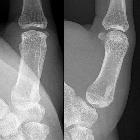

Osteom Finger

The imaging appearance reflects the underlying pathology, with ivory osteomas appearing as very radiodense lesions, similar to the normal cortex, whereas mature osteomas may demonstrate central marrow.